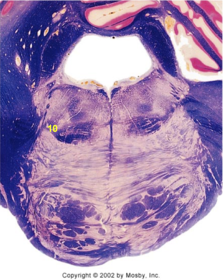

| Medullary pyramids | |

| Hypoglossal nucleus | |

| Hypoglossal nerve | |

| Dorsal motor nucleus of X | |

| Nucleus ambiguus | |

| Solitary tract | |

| Solitary nucleus | |

| ALS | |

| Medial lemniscus | |

| Medial longitudinal fasciculus | |

| Spinal tract of V | |

| Spinal nucleus of V | |

| Lateral (external, accessory) cuneate nucleus | |

| Anterior spinocerebellar tract | |

| CN IX | |

| Inferior cerebellar peduncle | |

| Inferior olivary complex | |

| Dorsal cochlear nucleus | |

| Inferior vestibular nucleus | |

| Medial vestibular nucleus | |